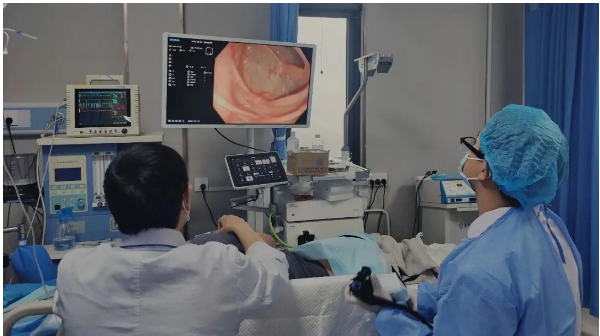

经无痛肠镜检查,吕主任发现李阿姨脾区肠壁增厚,肠道已经出现狭窄,肠镜无法顺利通过。随后取肿物进行活检,最终确诊为结肠癌。这个结果给李阿姨和她的家人敲响了警钟,也让我们深刻意识到,肠道发出的一些看似不起眼的信号,可能隐藏着致命的危机。

肠镜插入与观察:待患者进入睡眠状态后,医生会将带有摄像头的肠镜从肛门缓缓插入肠道,通过肠道蠕动逐步推进。在插入过程中,医生会不断注入少量空气,使肠道扩张,以便清晰地观察肠道黏膜的情况。肠镜上的摄像头会将肠道内部的画面实时传输到显示器上,医生可以仔细查看肠道内是否有息肉、炎症、溃疡、肿瘤等病变。如果发现可疑病变,医生还可以通过肠镜上的活检通道取少量组织进行病理检查,以明确病变的性质。